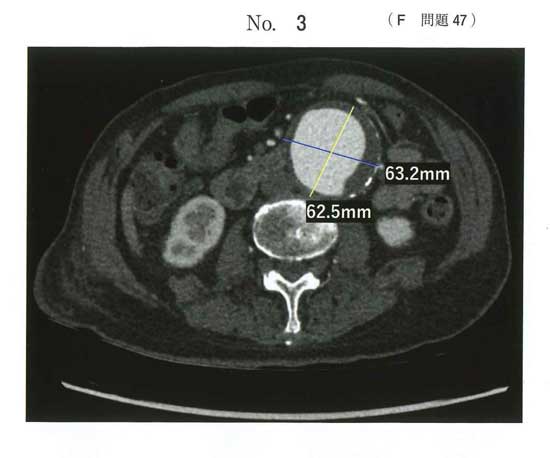

ステントグラフト治療は、高齢者や高リスク患者に対する大動脈瘤(腹部5cm以上、胸部6cm以上目安)の低侵襲治療として適しています。90歳以上でも全身状態が良ければ可能で、足の付け根から挿入し、体への負担が少なく、入院期間も短いのが最大の特徴です。